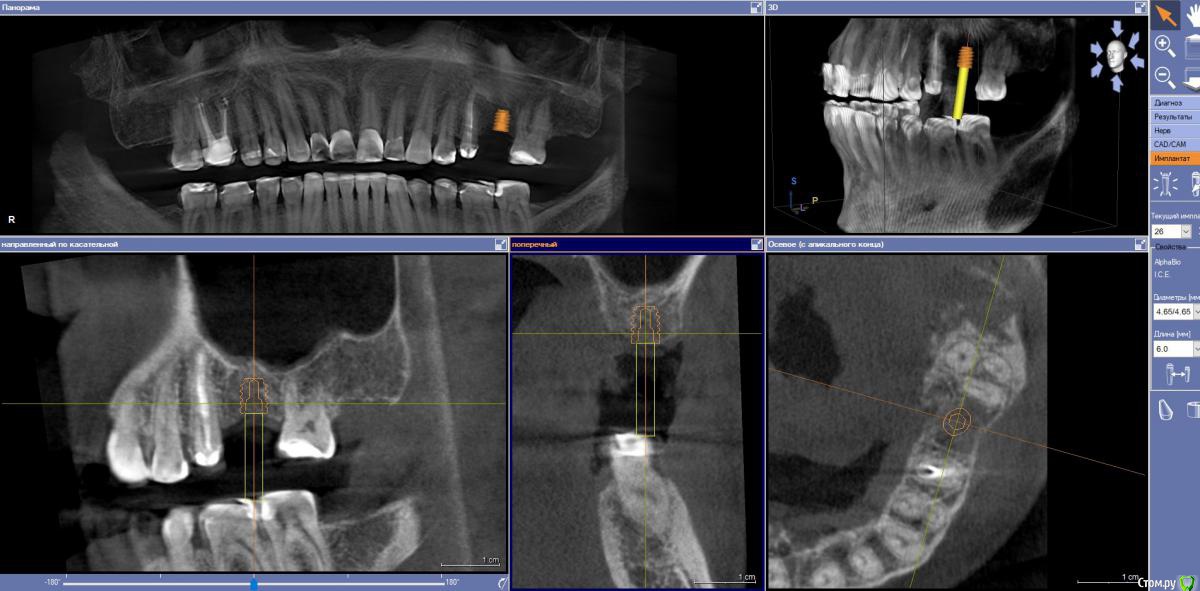

Ponchik Опубликовано 24 октября, 2017 Поделиться Опубликовано 24 октября, 2017 Как лучше поступить? Поставить покороче Альфа-Био 4.65-6 или Штрауманн 4.1-8 и постучать?Ортопеду всё равно, а я не могу определиться. Хочется поставить таки Штрауманн, но может это во мне жадность говорит и я всё усложняю? Ссылка на комментарий

Ponchik Опубликовано 24 октября, 2017 Автор Поделиться Опубликовано 24 октября, 2017 Возьмите Штрауманн 4.1х6 Со стандартом или стандартплюс не работал пока. Профильных сверл пока под них нет даже 8 и стучать не придется. Мне кажется 8 полностью не влезет, часть гребня при препарировании уйдет. 1-1.5мм стукнуть надо (вроде) А кто вам мешает поставить альфа био 4.2 на 8? А смысл? 8 у альфы короче чем 8 у штрауманна за счет формы апекса? Решил постучать и на это 5 2 причины (не связаны с клиникой):1) вредный пациент (так и стукнул бы )2) набор с остеотомами от штрауманна пылью покрылся. На самом деле больше интересует устойчивость таких 6мм товарищей от альфы, адекватно ли 4.2-6 или 4.65-6 в таком случае? Ссылка на комментарий

Тимур86 Опубликовано 24 октября, 2017 Поделиться Опубликовано 24 октября, 2017 6мм альфа био в живого человека...да ещё и на верхнюю челюсь!по мне рискованно 3 Ссылка на комментарий